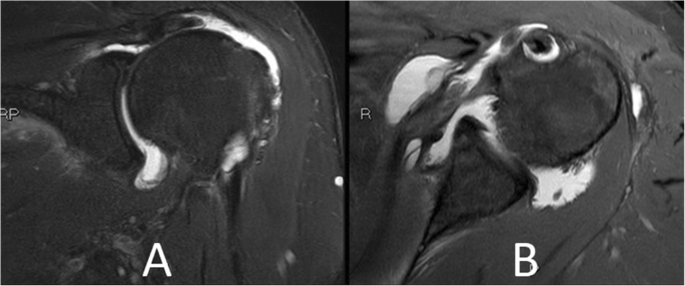

A 65-year-old female with a body mass index of 29 presented with a 7-month history of left shoulder pain and weakness. Physical exam and diagnostic imaging were consistent with a symptomatic full thickness rotator cuff tear of the supraspinatus and a partial tear of the subscapularis tendon (Fig. 1). She was indicated for an elective arthroscopic surgical repair. She was otherwise healthy with her only medical comorbidity consisting of hyperlipidemia. She had no prior surgical history including no prior shoulder procedures.